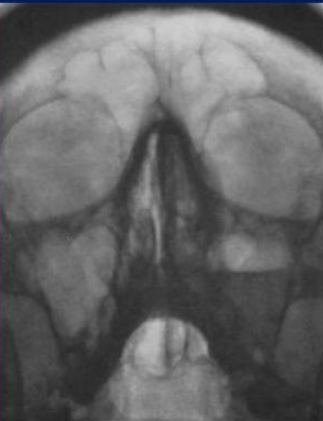

Изучение проблемы низкого качества рентгенограмм на Вашем оборудовании.